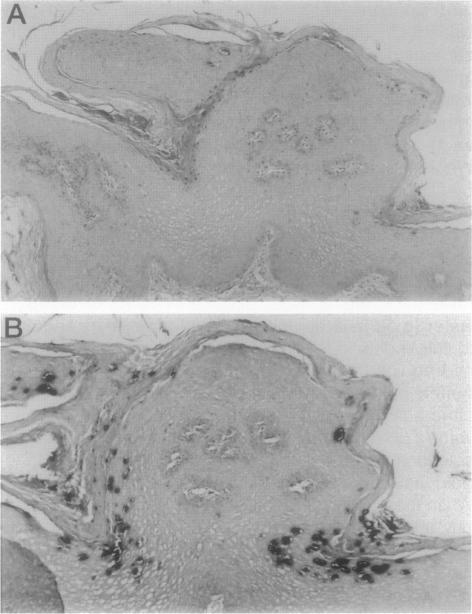

Neutral buffered formalin (NBF) (4% neutral buffered formaldehyde) has been advocated by most investigators as the primary fixative of choice for in situ hybridization (ISH), and specific anecdotal cautions interdicting the use of precipitating fixatives, which otherwise may offer certain advantages such as superior nuclear detail, are common. Few systematic studies addressing ISH fixation conditions have been published. We reasoned that heavy metals present in some precipitating fixatives may compromise duplex formation during ISH. Cell lines containing known viral gene content (CaSki, 200 to 600 human papilloma virus 16 copies/cell, and SiHa, 1 to 2 human papilloma virus 16 copies/cell) and two negative cell lines (K562 and MOLT 4) were expanded to >10(10) and pellets fixed in NBF, zinc formalin, B5, and Bouin's and Hollande's solutions, and subjected to DNA ISH using biotinylated genomic probes. Ten tissue biopsies fixed in both Hollande's and NBF solutions were also evaluated for human papilloma virus content using DNA ISH. Additionally, 17 cases of Hodgkin's disease fixed in B5 and formalin were compared for Epstein-Barr encoded RNA detection using RNA ISH with fluorescein isothiocyanate-labeled oligonucleotides. Catalyzed reporter deposition combined with Streptavidin-Nanogold staining and silver acetate autometallography (Catalyzed reporter deposition-Ng-autometallography ISH) and a conventional indirect alkaline phosphatase method were used for detection for both DNA and RNA. Contaminating heavy metals entrapped in fixed tissues were removed by two exposures to Lugol's iodine. Results for both DNA and RNA ISH comparing B5 and NBF fixatives were virtually identical. Hollande's, Bouin's, B5, and zinc formalin fixed tissue showed results indistinguishable from NBF fixed tissue in DNA ISH. Precipitating fixatives such as B5 and Hollande's solution may be used for DNA and RNA ISH under appropriate conditions.